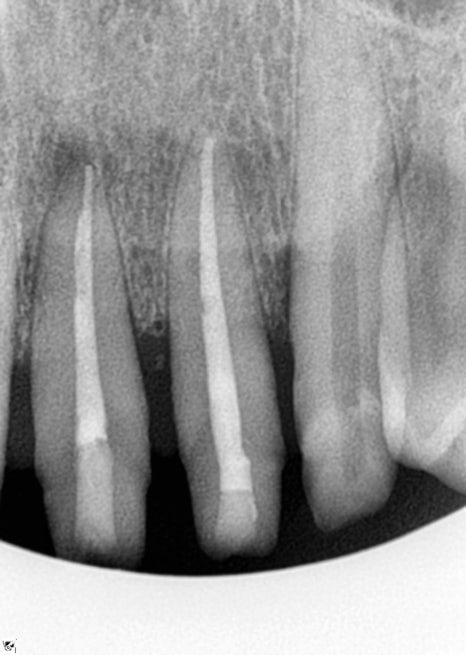

일단 파노라마 찍고 치근단 엑스레이

CT까지 확실히 촬영한 후 확인했습니다.

앞니 신경치료

앞니의 경우 보철물 치료를

진행을 할 계획이었는데요

1차 prep 후 환자분이 치아 시림 증상과

불편 증상을 호소하셔서

신경치료를 결정하게 되었습니다.

그 이유는 환자분이 앞니에서의 통증을

호소하셨기 때문인데요.

뿌리가 처음 방문 시부터 워낙 이미 짧기도

했던 부분이기에 신경치료로 진행을

하기로 결정했습니다.